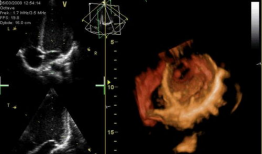

心脏跳动的视频,揭秘心脏跳动的奥秘

你知道吗?最近在网上流传着一个特别神奇的视频,它记录了心脏跳动的瞬间。这可不是普通的视频,它让我们仿佛能感受到心跳的力量,那种感...